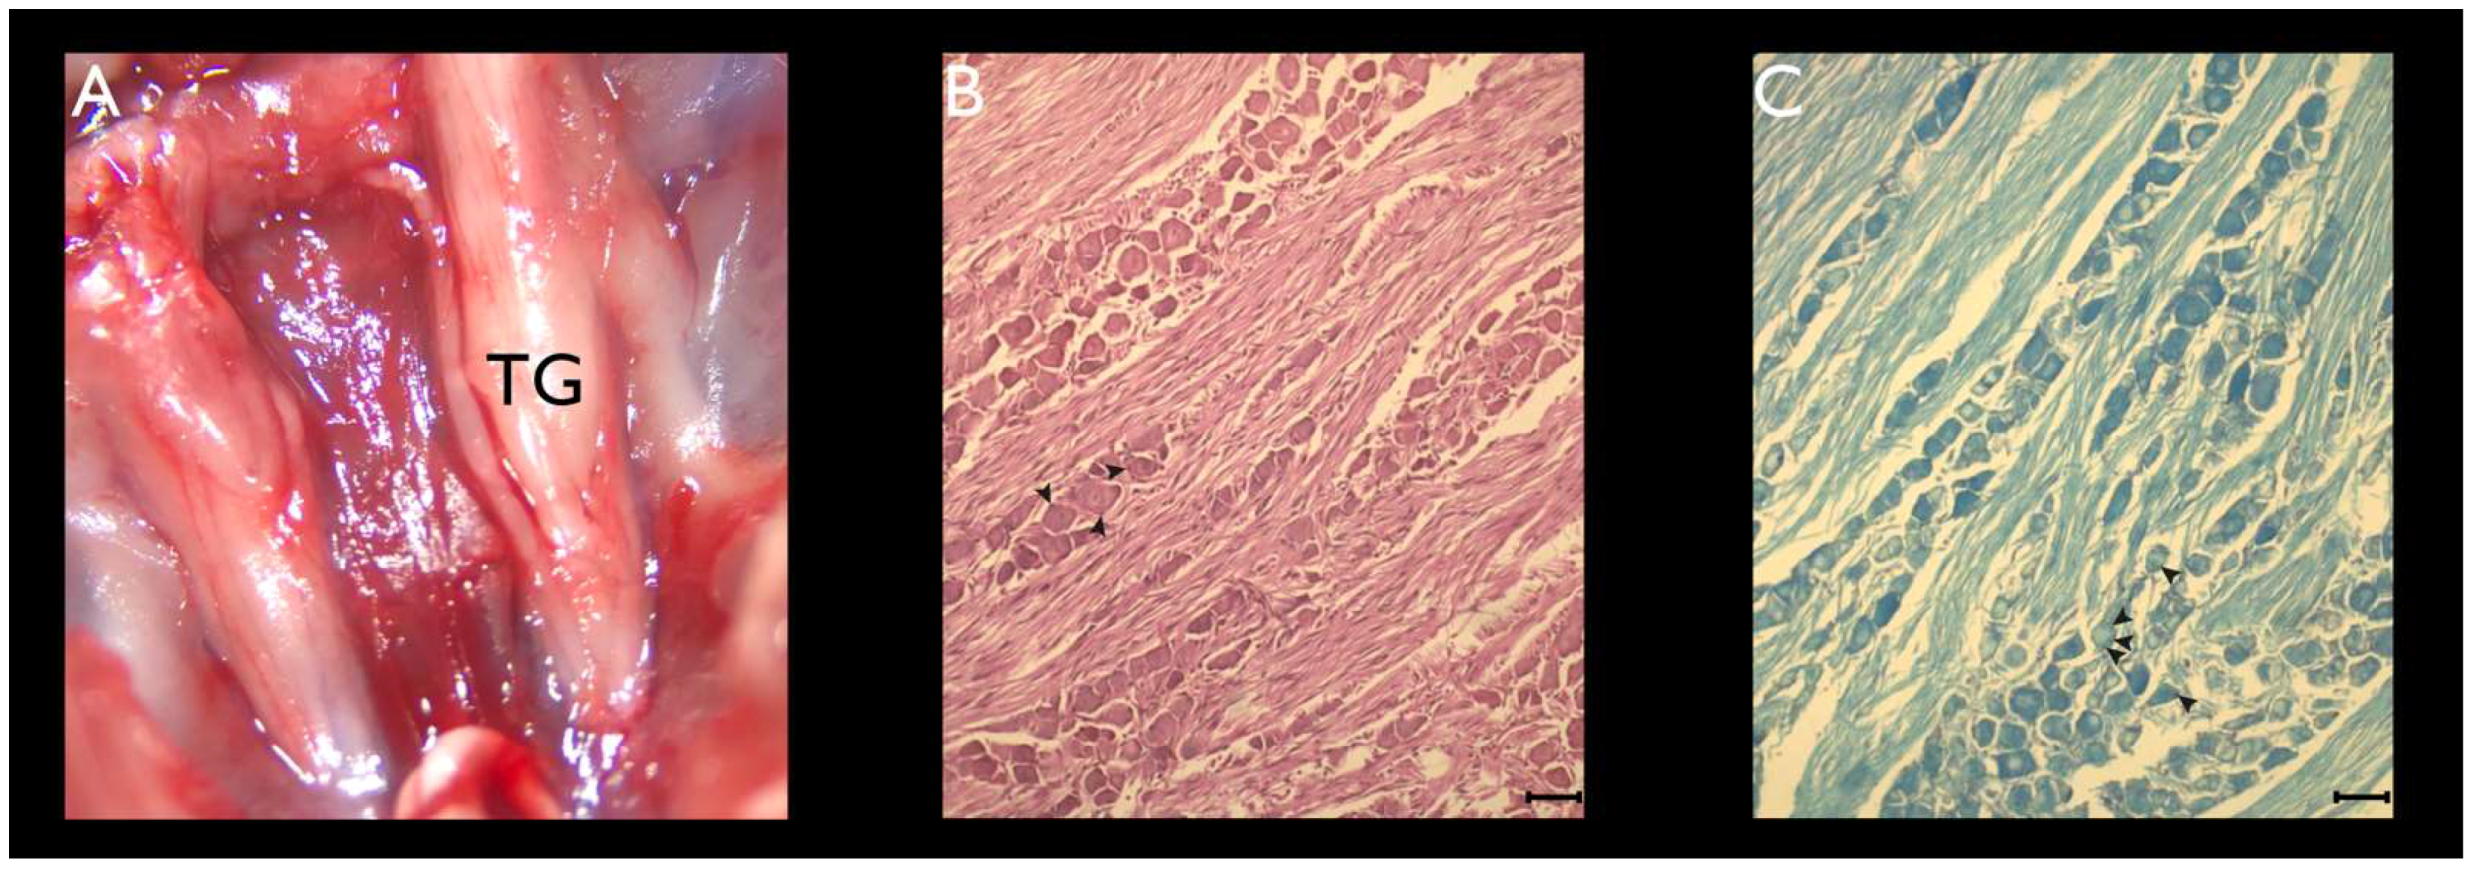

3.1. Histochemistry